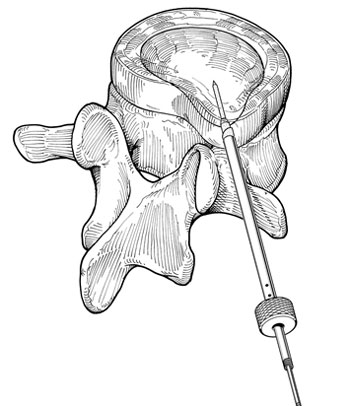

Após a introdução do fio guia procede-se com o dilatador, seguido da cânula, para finalmente poder introduzir o microressector, aparelho com o qual é realizada a ressecção do conteúdo do disco (Fig 5 a-e).

Fig. 5b